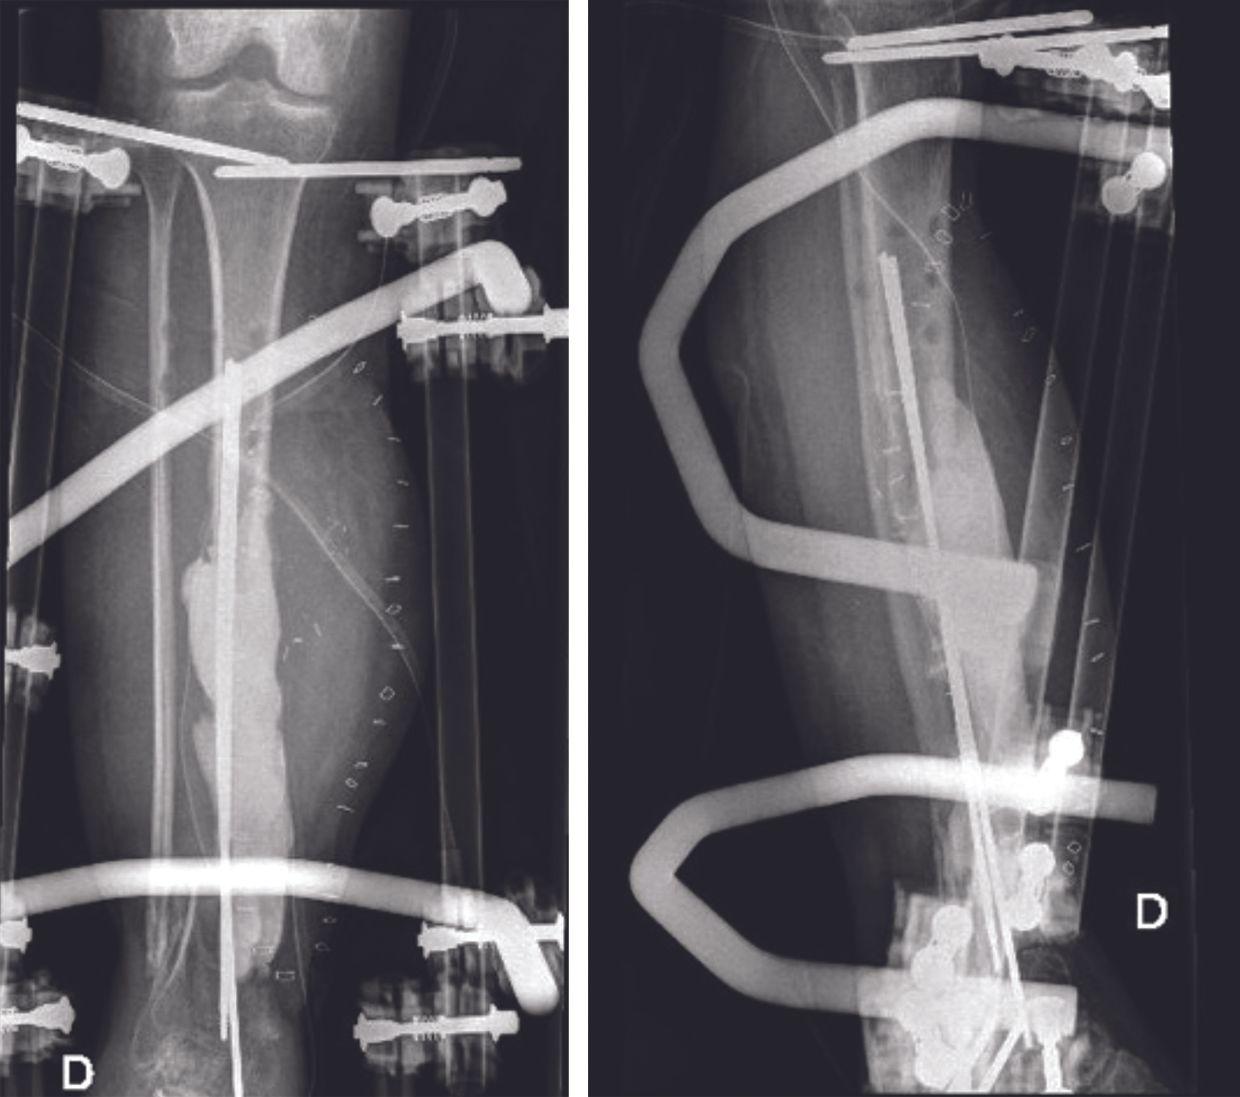

Gustilo III open fractures secondary to high-kinetic trauma pose two main treatment problems. Skin opening and injury to the soft tissues lead to a high risk of infection. Fractures, in particular those of the leg, may be accompanied by a major bone defect, requiring potentially complex bone reconstruction that may not be feasible at an early stage. In these circumstances, the use of a temporary antibiotic bone cement spacer provides benefits in the management of these two problems. When extensive soft tissue lesions associated with bone defects of varying dimensions are present (Fig. 1 and 2), amputation may be discussed as a salvage procedure.

For these reconstruction cases many surgeons prefer the Masquelet technique in this situation. Following emergency care, the first surgical stage consists of bone debridement, inserting an antibiotic bone cement spacer and immobilizing the limb with an external fixator (or performing a temporary osteosynthesis) (Fig 3). Once the fracture location is stabilized, the soft tissue lesions can be managed, by extensive debridement followed by flap coverage, and treating any infection with local and systemic antibiotics. The Masquelet technique builds an induced membrane around the cement spacer within a month.

The second surgical stage includes removal of the cement spacer, bony reconstruction by bone grafting and final osteosynthesis (Fig. 4 and 5). The spacer is replaced by bone grafts harvested using the RIA (reamer – irrigator – aspirator) technique. The RIA technique allows large amounts of quality bone graft to be harvested if necessary. The induced membrane of the Masquelet technique avoids resorption of the bone graft and allows secondary bone healing.